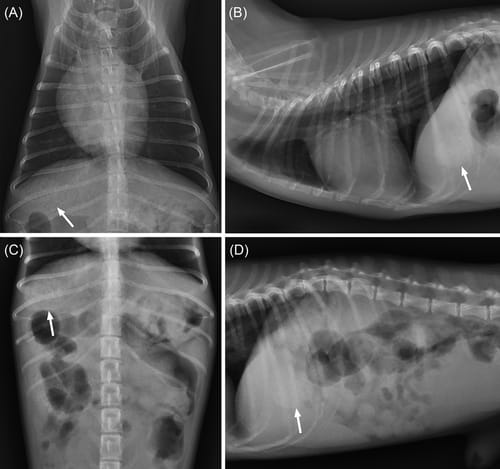

Evaluation of increased opacity in the region of the gallbladder during radiographic examination in dogs. Increased opacity of gallbladder (arrows) on thoracic ventrodorsal (A), and right lateral (B) views, and abdominal ventrodorsal (C), and right lateral (D) views are detected. Radiographs were taken using 2.0 mAs and 66 kVp for thorax (A, B) and 3.2 mAs and 60 kVp for abdomen (C, D).

Results: They found that increased radiographic opacity in the region of the gallbladder was associated with large amounts of sediment, sludge balls, or gallbladder mucocele on ultrasound. They also found that the thoracic ventrodorsal view had the highest sensitivity for detecting gallbladder sediment on radiograph.

Conclusions: The study concluded that large amounts of sediment, sludge balls, or mucoceles can cause increased opacity in the region of the gallbladder on radiography and that the thoracic ventrodorsal view is recommended to evaluate gallbladder opacity.